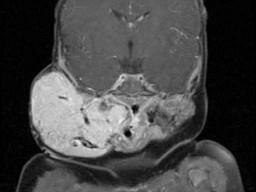

问题 老年患者,右侧面部肿胀,呈青紫色,MRI检查如图所示,请选择最可能的诊断 ( )

选项 A、神经纤维瘤 B、神经鞘瘤 C、囊肿 D、脓肿 E、血管瘤

答案 E